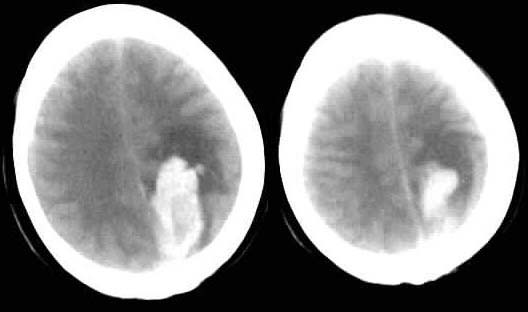

随访结果:

病人第二天做mr并增强,未见脑肿瘤,诊断为脑出血。

第四天ct复查,血肿较第一次ct增大。

谢谢roadtofree楼主的跟踪随访,学习并长见识了。现在看来,我原来太主观了,对不起各位老师啊,惭愧!至于我所考虑的那些不支持新鲜出血的表现,扬仪战友的意见可以给出答案。楼主的随访“第四天ct复查,血肿较第一次ct最大”,明确的支持这一论断。向楼主致敬,并向扬仪战友学习!也向批评我的lkc1693等诸位老师说声:对不起!我会从中汲取教训的。